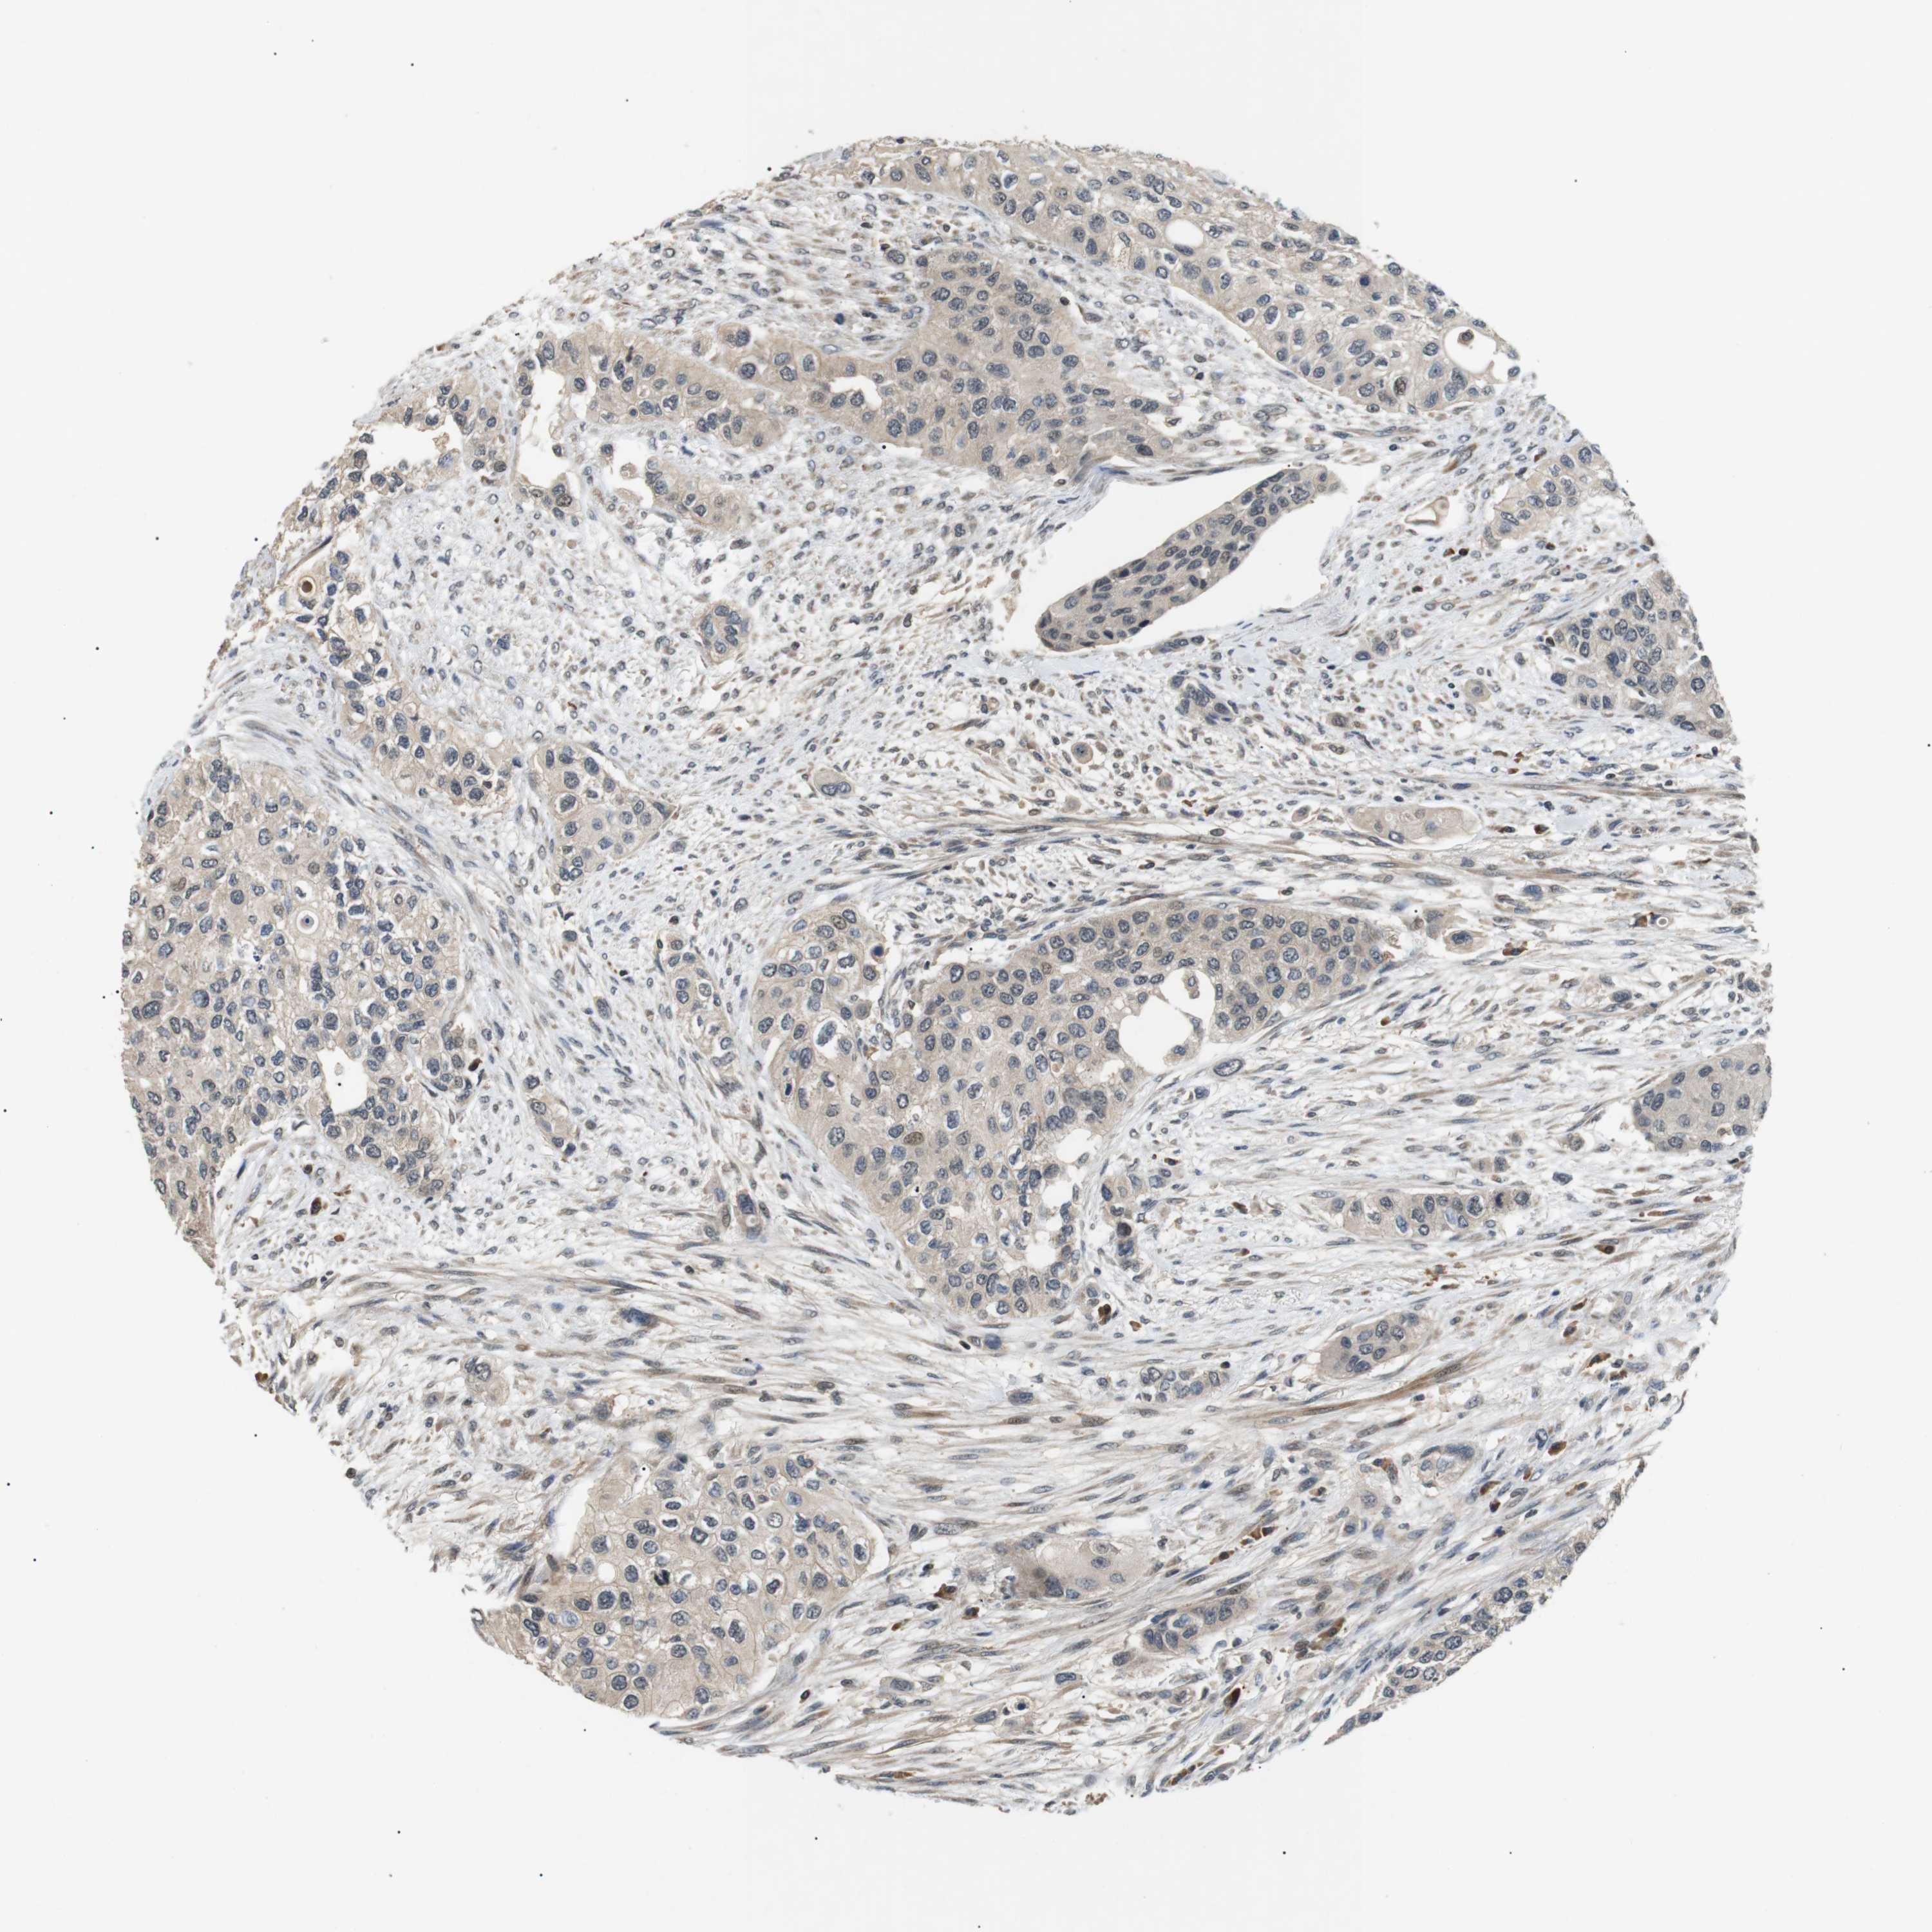

UROTHELIAL CANCER - Protein expressioni

A mouse-over function shows sample information and annotation data. Click on an image to view it in a full screen mode. Samples can be filtered based on level of antibody staining by selecting one or several of the following categories: high, medium, low and not detected. The assay and annotation is described here.

Note that samples used for immunohistochemistry by the Human Protein Atlas do not correspond to samples in the TCGA dataset.

Antibody stainingi

Antibody staining in the annotated cell types in the current human tissue is reported as not detected, low, medium, or high, based on conventional immunohistochemistry profiling in selected tissues. This score is based on the combination of the staining intensity and fraction of stained cells.

Each image is clickable and will lead to virtual microscopy that enables deeper exploration of all samples and also displays staining intensity scores, fraction scores and subcellular localization as well as patient and tissue information for each sample.

Antibody HPA014797

Staining

High

Medium

Low

Not detected

Intensity

Strong

Moderate

Weak

Negative

Quantity

>75%

75%-25%

<25%

None

Location

Nuclear

Cytoplasmic/membranous

Cytoplasmic/membranous,nuclear

Urothelial carcinoma, High grade

Urothelial carcinoma, Low grade